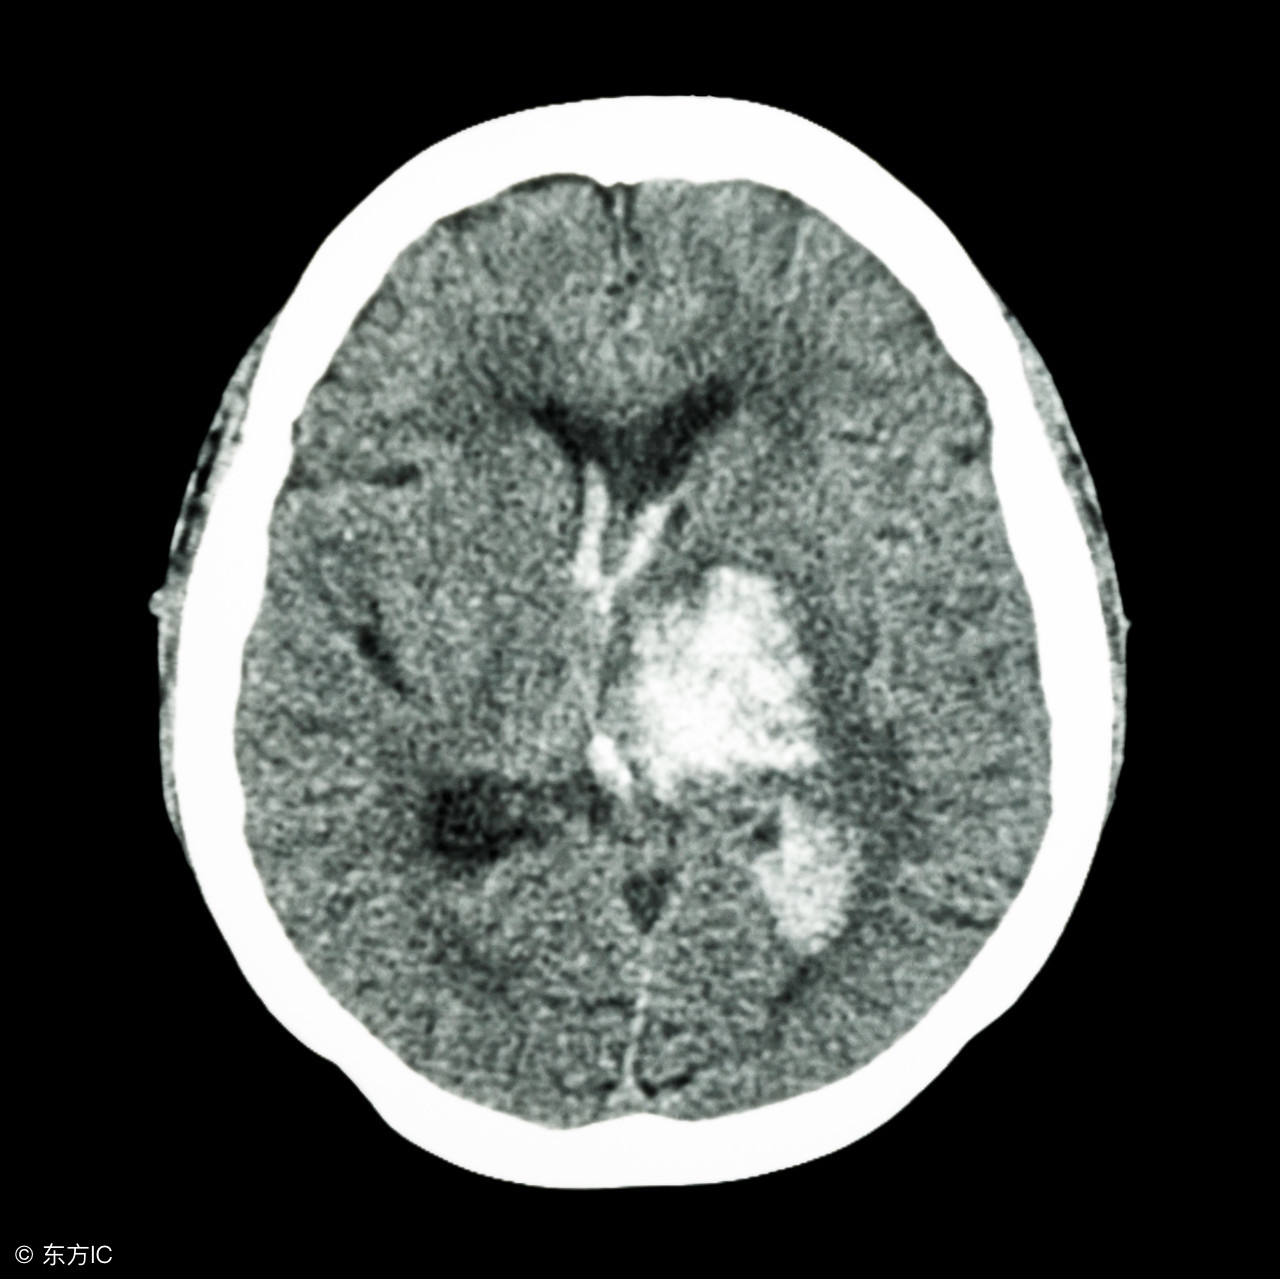

高血压脑出血手术后的饮食

注:文中图片来自网络,如有侵权请联系删除